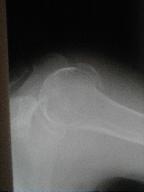

上腕骨頚部骨折 その2